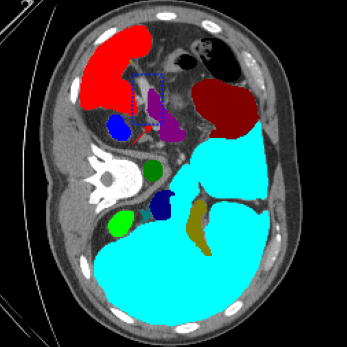

| Ground Truth | LoGoNet | DiNTS Search |

|---|---|---|

![]() |

We begin by qualitatively inspecting our model. Figure 3 compares the output of LoGoNet to the best performing baseline model in BTCV dataset, i.e., DiNTS Search (more qualitative comparisons can be found in appendix section 11). We see that our model particularly excels in segmenting organ boundaries. This can be attributed to our effective strategy for extracting local-range dependencies, which plays a crucial role in extracting details from input data. Our model’s adeptness in capturing long-range dependencies allows it to grasp contextual information that extends over significant distances within the data. Simultaneously, its proficiency in handling short-range dependencies ensures precision in capturing localized patterns.